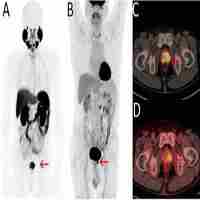

| Abstract | Positron emission tomography/computed tomography (PET/CT) is widely used in prostate cancer to evaluate the localized tumor burden and detect symptomatic metastatic lesions early. 18F-FDG is the most used tracer for oncologic imaging, but it has limitations in detecting early-stage prostate cancer. 68Ga-PSMA is a new tracer that has high specificity and sensibility in detecting local and metastatic tumors. But with the progression of prostate cancer, the enhancement of glucose metabolism in progressive prostate cancer provides a chance for 18F-FDG. This review focuses on PET/CT in the detection and prognosis of prostate cancer, summarizing the literature on 18F-FDG and 68Ga-PSMA in prostate cancer and highlighting that 18F-FDG has advantages in detecting local recurrence, visceral and lymph node metastases compared to 68Ga-PSMA in partial progressive prostate cancer and castration-resistant prostate cancer patients. We emphasize 18F-FDG PET/CT can compensate for the weakness of 68Ga-PSMA PET/CT in progressive prostate cancer. |